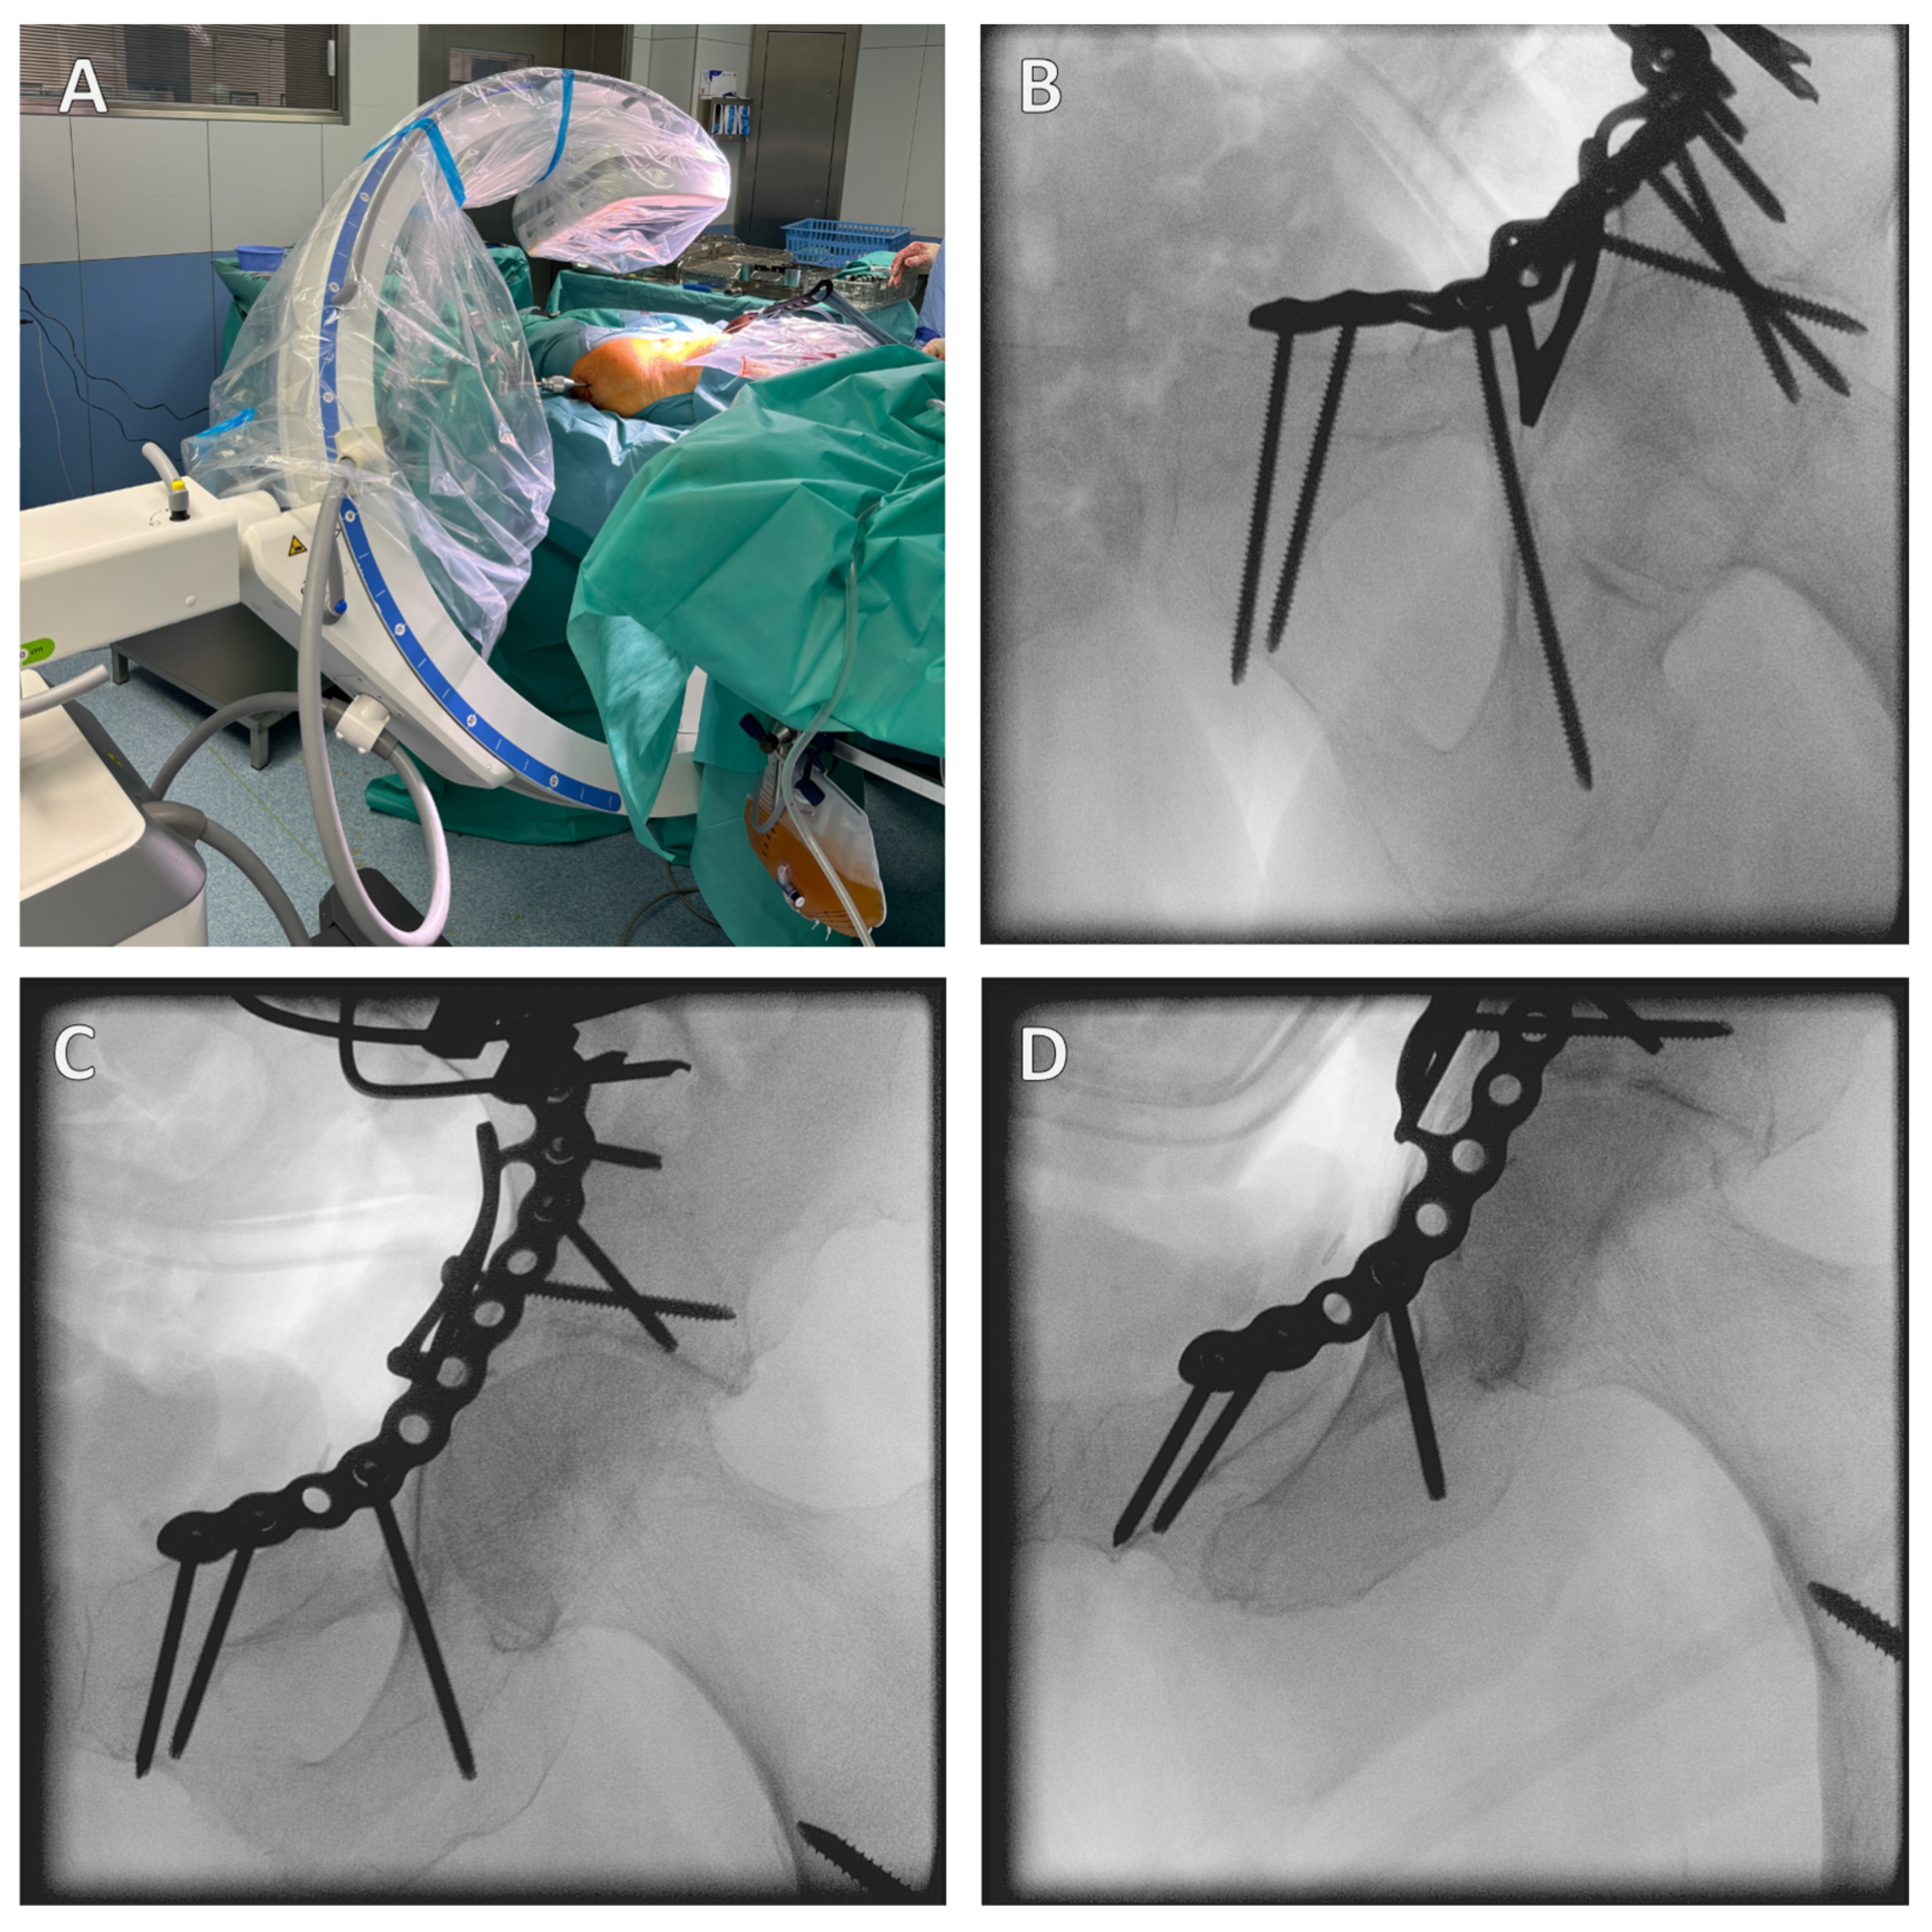

The mechanism of the fracture is as follows: a fall from a standing position causes a lateral fall onto the hip. This results in a transfer of force from the greater trochanter via the femoral neck to the femoral head, where the force is then transmitted to the anterior superior in the acetabulum itself due to the femoral anatomy (Figure 1).

Figure 1. Fracture mechanism of a geriatric acetabular fracture. A fall from a standing position to the side results in a transfer of force from the greater trochanter via the femoral neck to the femoral head, where the force is then transferred to the anterior superior into the acetabulum. A reduced bone density causes the acetabulum to collapse/fracture. The red arrow in the illustration shows the force trajectory, from the right lateral (A), anterior (B), and left anterolateral views (C).